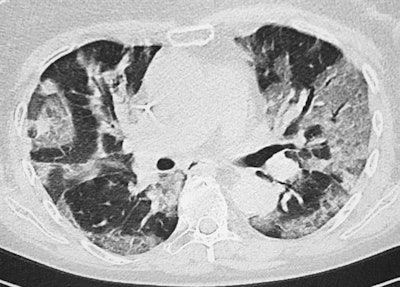

Thanks to the national and international publications and information campaigns, we have become quite aware of the COVID-19 CT features, but soon we had quite a lot of nontypical cases, including patients with extrathoracic findings or severe cases in young people. We have also had some patients from our hemodialysis center presenting with less severe cases and many patients with ear, nose, and throat symptoms or associated diseases, including pulmonary emboli. This is quite a problem in COVID-19 cases that require cooperation with clinicians, especially emergency specialists.